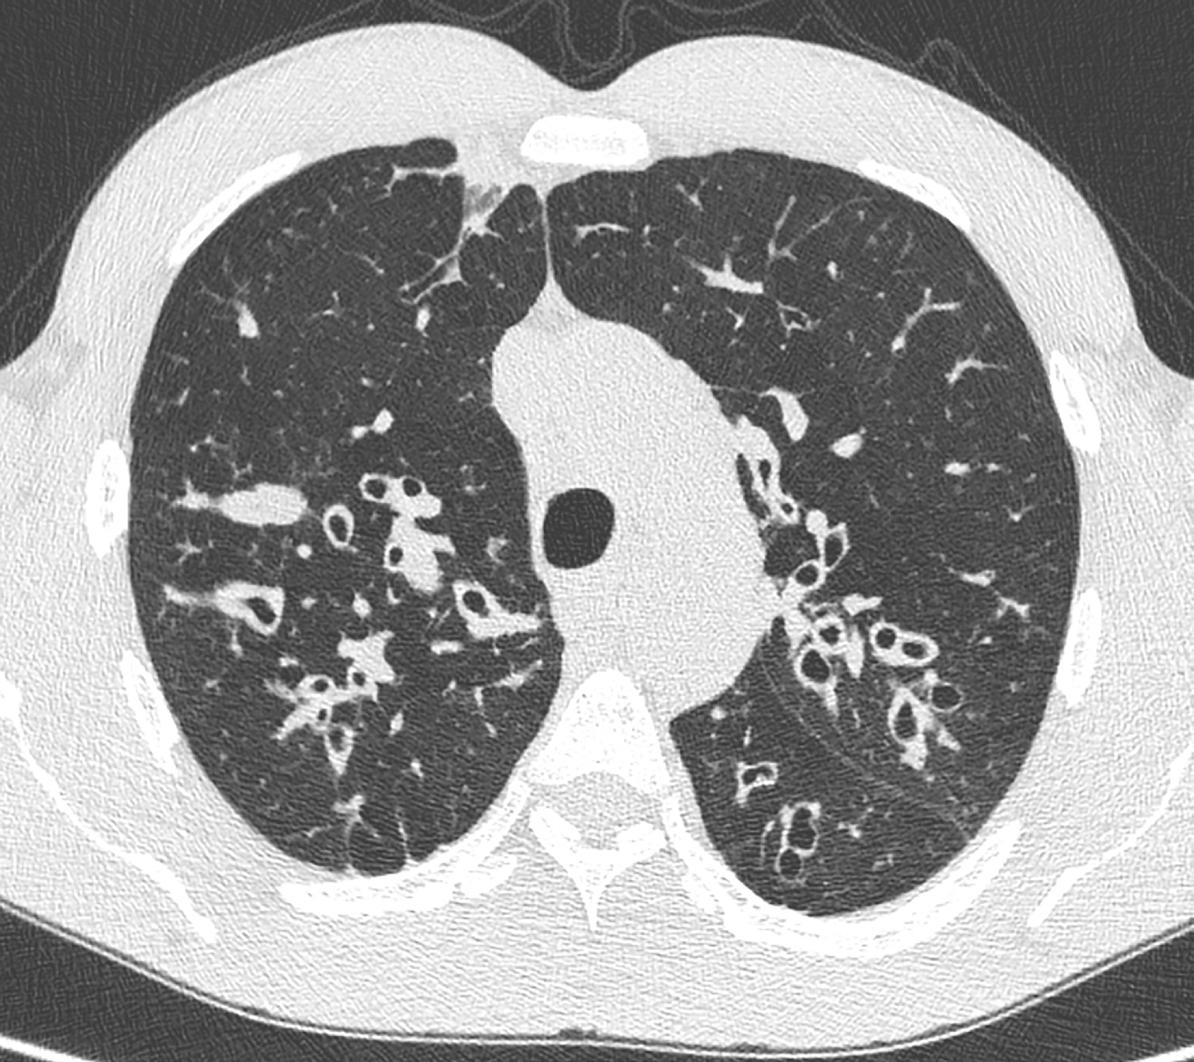

foreløpig Bilde 3: Vasospasme. Dag 1 ses ikke holdepunkter for vasospasme, mens vasospasme er uttalt på dag 7. Sees som innsnevring/ kaliberveksling av karet. Til tross for tiltak i form av både økt cerebral perfusjonstrykk og intraarteriell nimotop utviklet pasienten bilaterale anteriore infarkt (hypodense område på CT caput til høyre på dag 12)